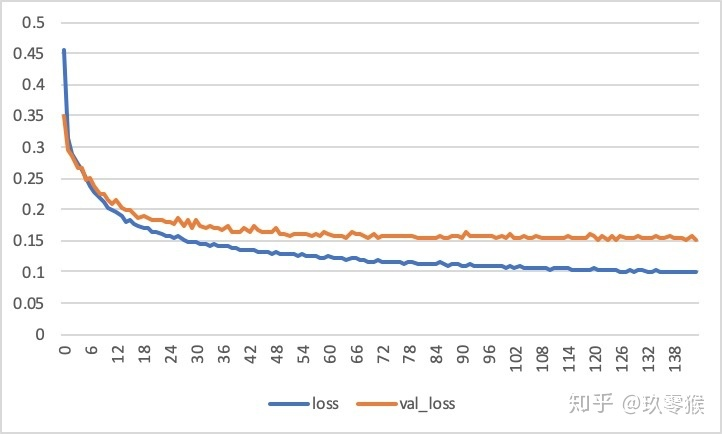

每一次epoch训练结束,都会对验证集进行测试Iou指标,如果比之前最好的还要好就保存本次训练模型,如果超过args.early_stop这个参数还没有训练更好的话,便结束训练,这个原理就是early_stop,主要还是防止网络训练过度,造成过拟合现象,这也就是验证集虽然没有直接参与训练,但是却在其中扮演了一个非常重要的角色!

运行的结果: